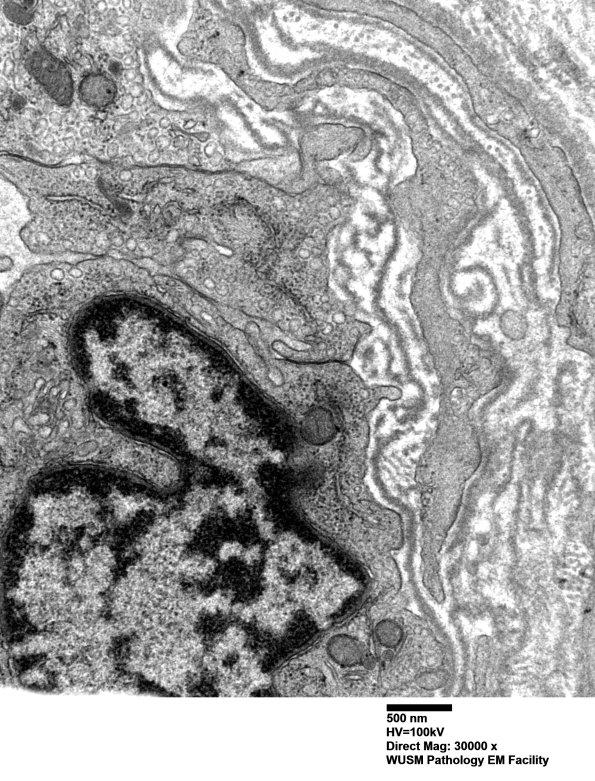

There are numerous fragments of basal membranes within the abnormal vessel wall. (electron micrographs) ---- Interpretation: A diagnosis of humoral immune microvasculopathy (HIEM) was made on this nerve with C5b-9 deposited on some endoneurial microvessels.